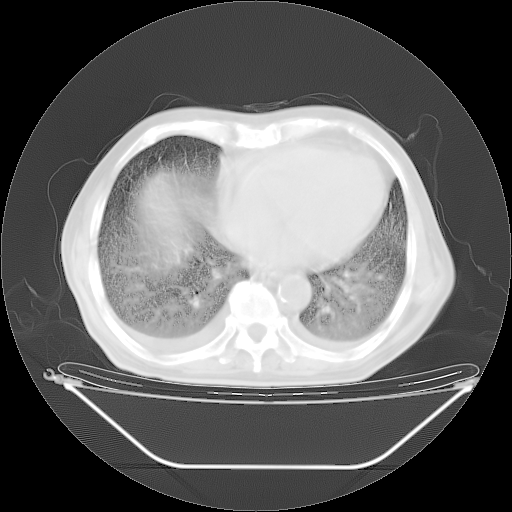

今天复查肺部CT,发现双肺广泛磨玻璃样改变。所以我把3月19日和5月9日相隔50天的肺部CT上传。请大家会诊。

5月9日肺部CT(在4月27日齐鲁医院肺部CT描述部分肺组织磨玻璃样改变,12天后肺组织广泛磨玻璃样改变)

大致读了系列胸部CT:纵隔窗无明显异常,肺窗:从4、27至今:主要是双肺中下野外带可见毛玻璃样改变,目前处于急性肺泡炎阶段,至于原因考虑1、结替组织或胶原血管性疾病所致?2、恶性疾病如恶组在肺部所致的表现或细支气管肺泡癌?3、药物或其它原因如肺蛋白沉着症所致肺泡炎目前不太可能?总之,明天就去请我院的呼吸科、感染科、血液科和临免专家会诊哈。